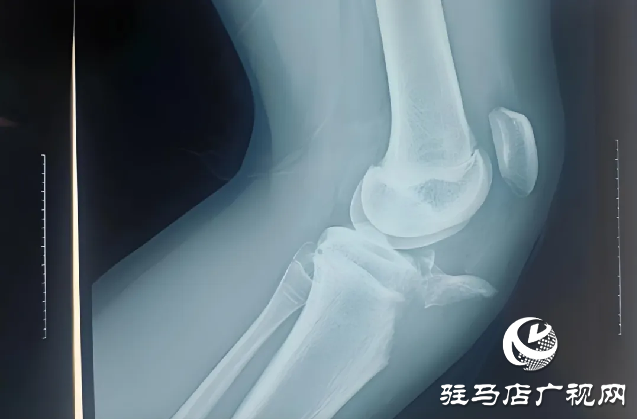

近日,胡同學(xué)在學(xué)校上樓梯時(shí)不慎摔倒,傷后感到左膝疼痛不適,活動(dòng)不能,家人緊急送他來駐馬店市第一人民醫(yī)院骨科二病區(qū)。入院后完善相關(guān)檢查,任耀醫(yī)生根據(jù)胡同學(xué)的病情、影像學(xué)、術(shù)前檢查,做出診斷:左脛骨結(jié)節(jié)撕脫性骨折;左髕韌帶斷裂。

駐馬店市第一人民醫(yī)院任耀醫(yī)生提醒,脛骨結(jié)節(jié)撕脫骨折屬運(yùn)動(dòng)損傷,較少見,好發(fā)于12-17歲男性青少年。損傷機(jī)制為股四頭收縮(向心,離心)牽拉致傷,常見于加速跑,起跳,落地等發(fā)力瞬間,根據(jù)X線片骨折線走行及移位情況分為3型。臨床表現(xiàn)為疼痛,主動(dòng)伸膝行走、負(fù)重不能,X線可見脛骨結(jié)節(jié)骨折,髕骨上移,有時(shí)可合并髕腱斷裂。